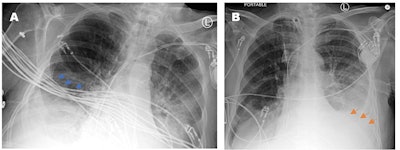

Portable chest x-rays have become widely used in hospitals across the U.S., not only for patients who are too sick to be transferred to the radiology department but also for routine floor patients. Patient rotation, foreign body overlying anatomy, and anatomy out of the field of view can have detrimental impacts on the quality of these exams.

In addition, 43.5% of the problematic films with a repeat portable chest x-ray within one week showed there were technical problems impacting the ability to detect pathology. Key issues that led to poor image quality included improper patient positioning, foreign objects covering anatomy, and variances in technologists' training, the authors wrote.

One key issue was that some technologists did not have the physical strength to move sick and overweight patients in ICU beds, resulting in poor image quality, the authors found. Also, when certain machines, medical devices, and wires interfered with their ability to capture images, technologists were often unsure about how each of the medical devices could be moved appropriately.